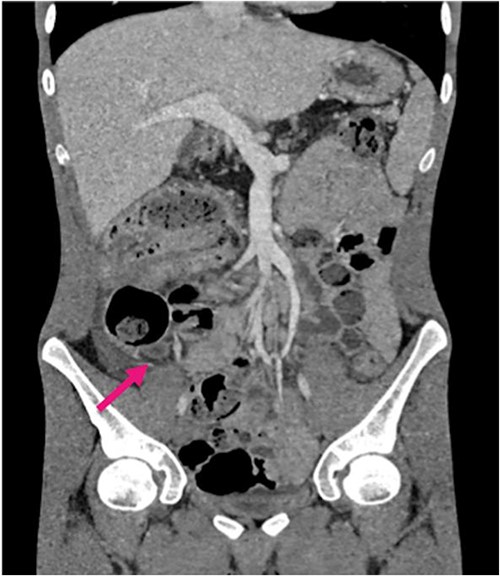

Radiological investigations included a contrast computerized-tomography (CT) of the abdomen/pelvis and suggestive of intussusception of the caecum into the ascending colon, with a thickened appendix. Due to the presence of faecal loading, it was not clear radiologically whether the combined clinical picture was suggestive of distal intestinal syndrome (Figs 1 and 2) due to faecal loading only, or true intussusception of the appendix.

Contrast CT axial sections showing the enhanced thickened appendix (white) intussuscepts with fat stranding, into the ascending colon. Distal faecal loading also observed.

Contrast CT coronal sections depicting the classical ‘bullseye sign’ of intussusception of the caecum into the ascending colon.